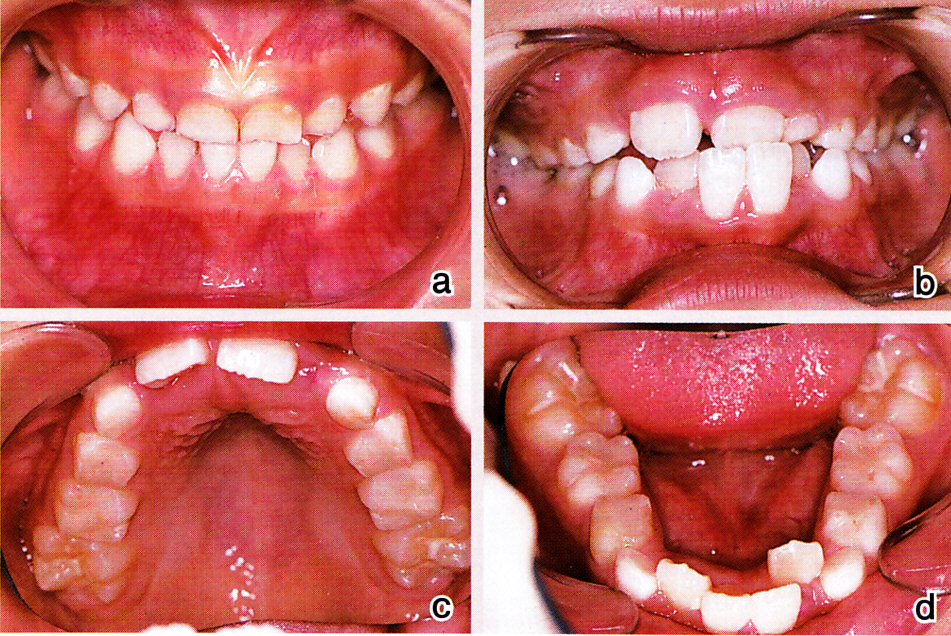

側切歯が舌側に出て叢生となり、この状態を放置すると、たいていの場合、前歯の叢生はそのままに、あるいはもっとひどくなりながら側方歯群の交換が進み、歯列のどこにも隙間はなくなってしまいます(図1:症例Ⅰ)。場合によっては、小臼歯を抜去し、かつ矯正が必要となるでしょう。できれば、将来の抜歯は避けたい、そのために、積極的に乳犬歯間幅径を拡大する試みを行っています。

症例Ⅲは、前歯の交換時期に叢生をきたした患児です。

図11 a:初診時3歳 隙間の全くない乳歯列。甘いもの好きで、あまり噛まない子供だった

b:7歳 右下2番から左下2番まで叢生。上下左右1番反対咬合

c:7歳 上顎・・・・側切歯のスペース不足

d:7歳 下顎・・・・側切歯が乳犬歯舌側に重なって出て、W型の叢生となった。